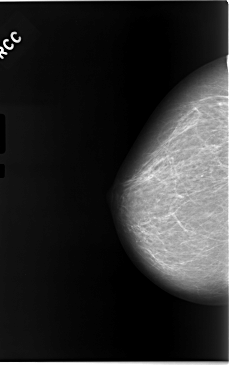

C_0046_1.RIGHT_CC

RIGHT_CC LINES 5840 PIXELS_PER_LINE 3664 BITS_PER_PIXEL 12 RESOLUTION 50 NON_OVERLAY